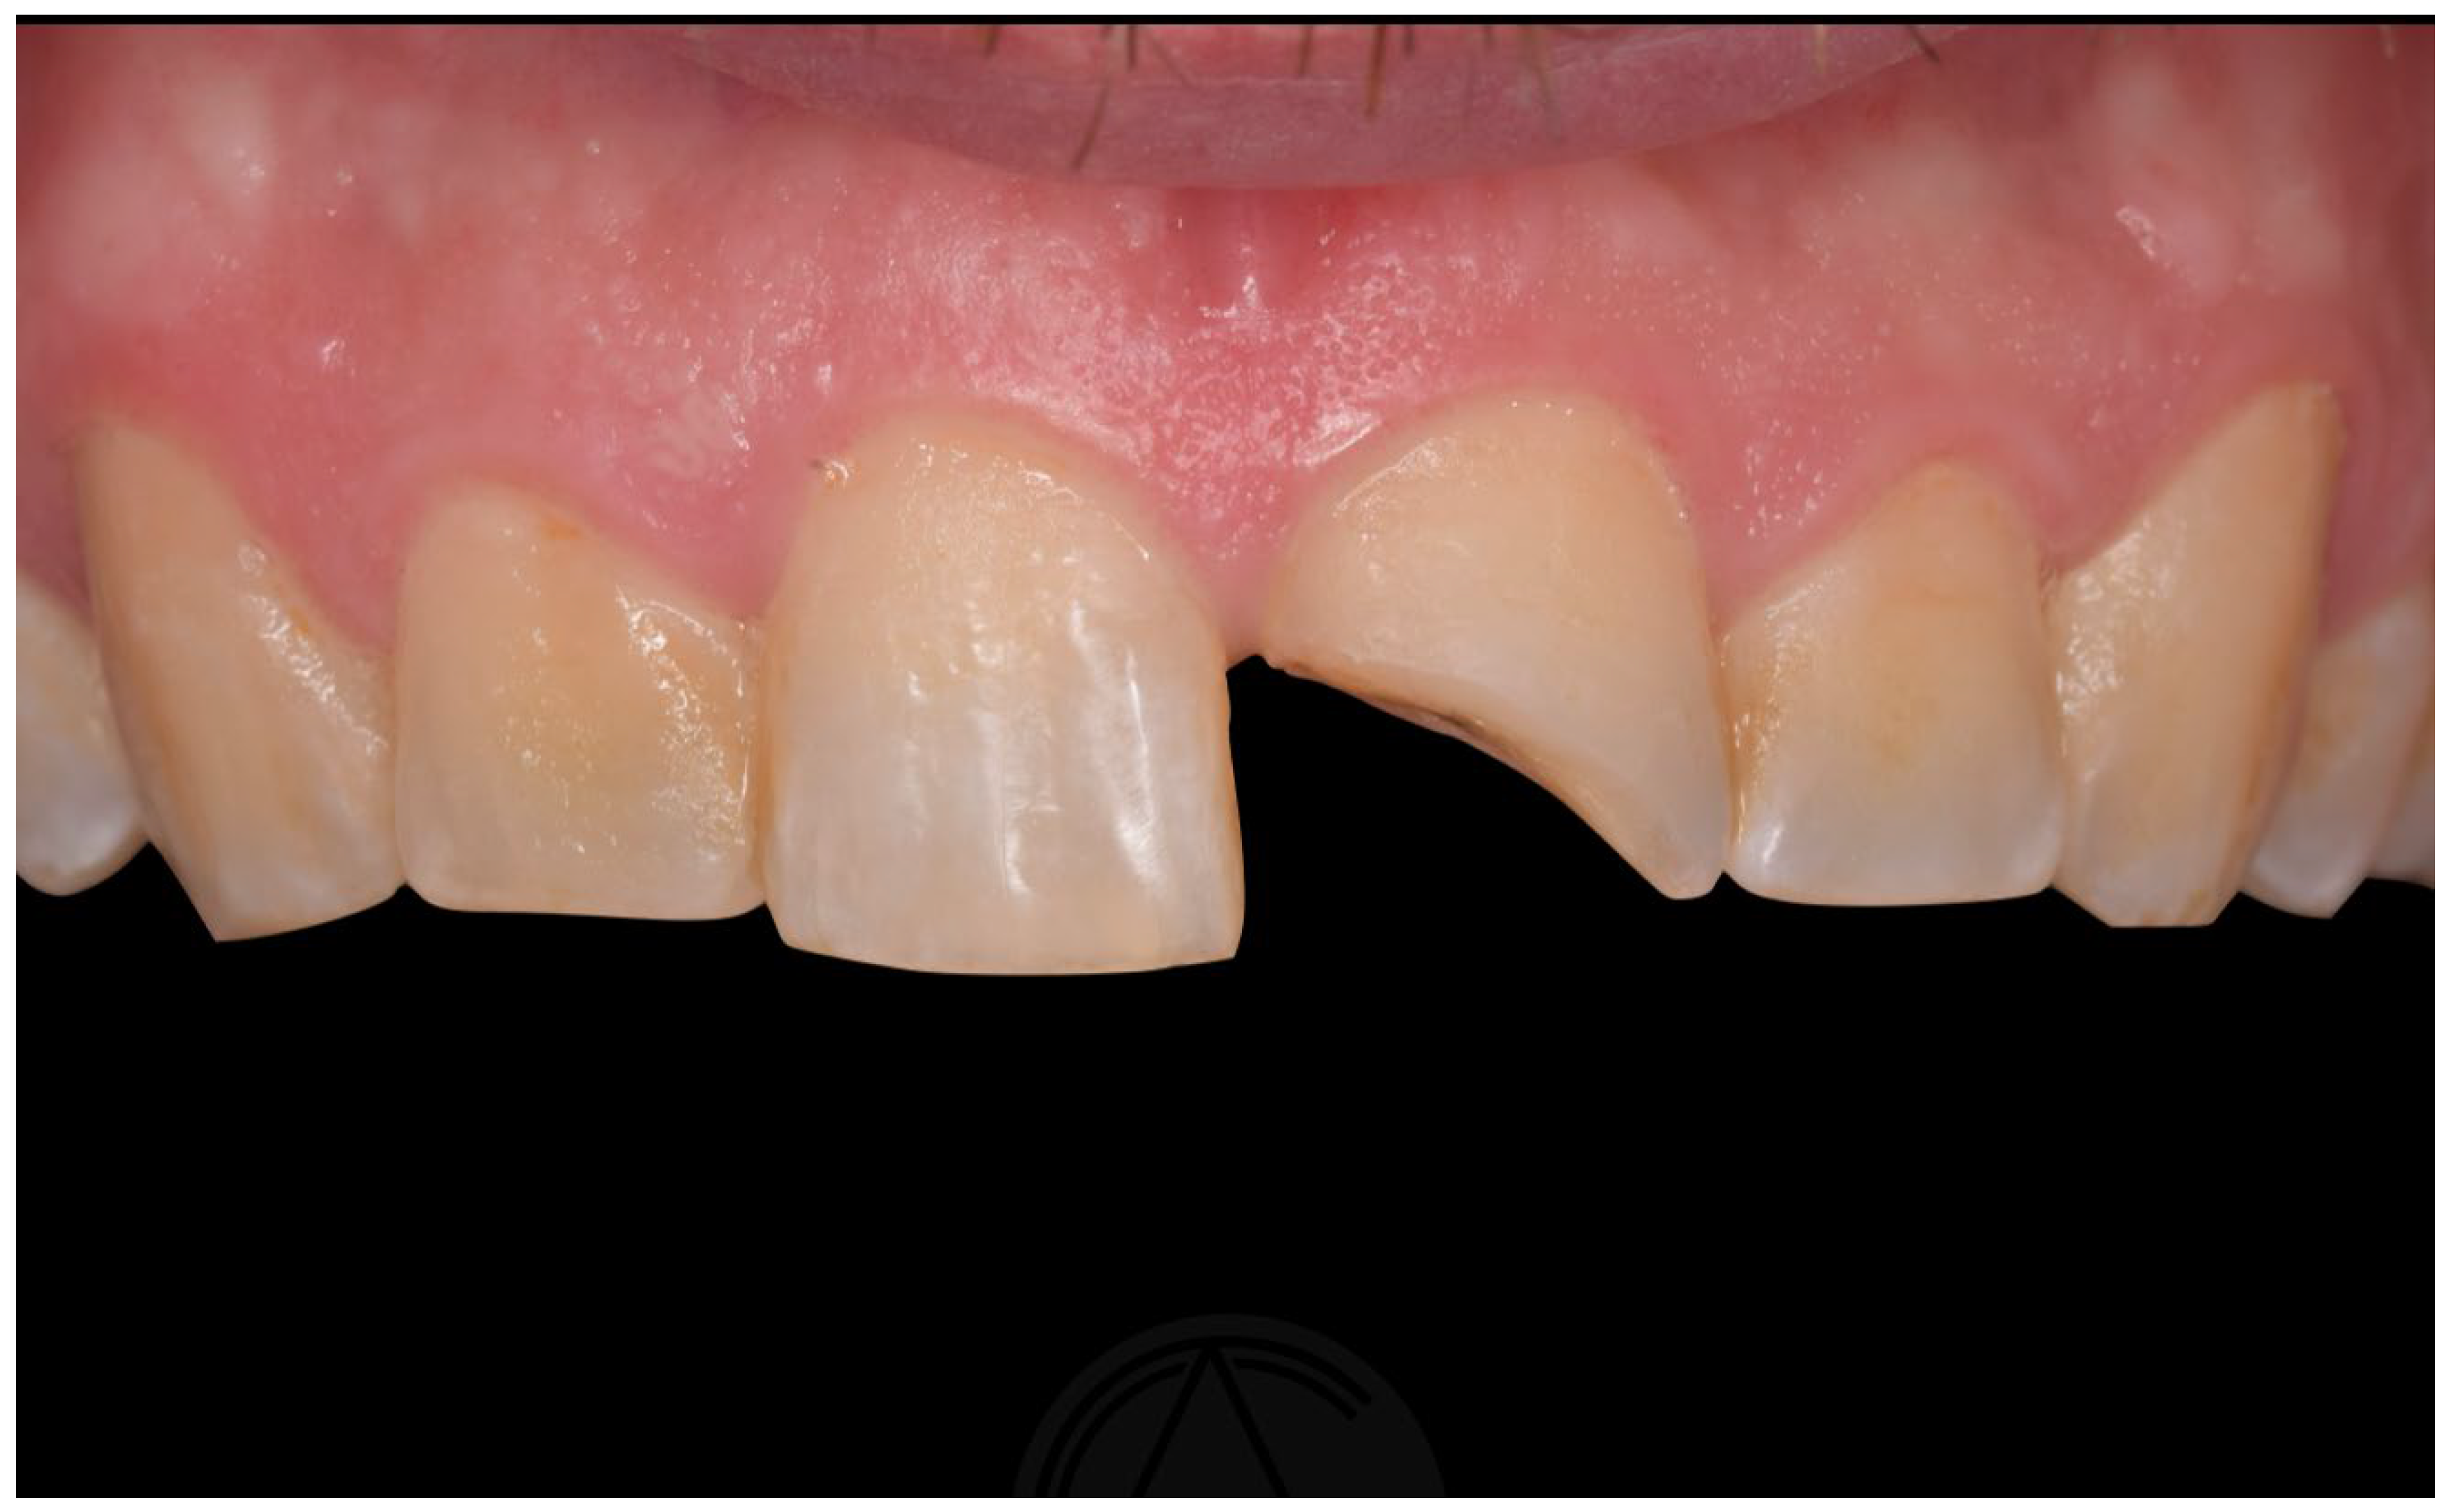

5. Oblique Fractures

- 1.

- Supragingival

5.1. No Pulp Involvement

- Treatment option: Adhesive dentistry.

5.2. With Pulpal Involvement

- Treatment options: Endodontic Treatment and Adhesive dentistry.